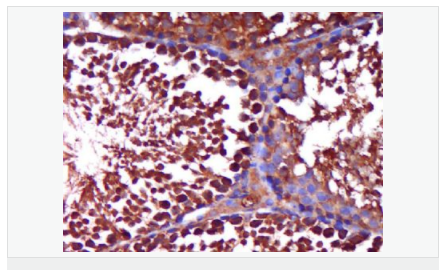

| 產(chǎn)品介紹 | The androgen receptor gene is more than 90 kb long and codes for a protein that has 3 major functional domains: the N-terminal domain, DNA-binding domain, and androgen-binding domain. The protein functions as a steroid-hormone activated transcription factor. Upon binding the hormone ligand, the receptor dissociates from accessory proteins, translocates into the nucleus, dimerizes, and then stimulates transcription of androgen responsive genes. This gene contains 2 polymorphic trinucleotide repeat segments that encode polyglutamine and polyglycine tracts in the N-terminal transactivation domain of its protein. Expansion of the polyglutamine tract causes spinal bulbar muscular atrophy (Kennedy disease). Mutations in this gene are also associated with complete androgen insensitivity (CAIS). Two alternatively spliced variants encoding distinct isoforms have been described. [provided by RefSeq, Jul 2008] Function: Steroid hormone receptors are ligand-activated transcription factors that regulate eukaryotic gene expression and affect cellular proliferation and differentiation in target tissues. Transcription factor activity is modulated by bound coactivator and corepressor proteins. Transcription activation is down-regulated by NR0B2. Activated, but not phosphorylated, by HIPK3 and ZIPK/DAPK3. [ENZYME REGULATION] AIM-100 (4-amino-5,6-biaryl-furo[2,3-d]pyrimidine) suppresses TNK2-mediated phosphorylation at Tyr-267. Inhibits the binding of the Tyr-267 phosphorylated form to androgen-responsive enhancers (AREs) and its transcriptional activity. Subunit: Binds DNA as a homodimer. Part of a ternary complex containing AR, EFCAB6/DJBP and PARK7. Interacts with HIPK3 and NR0B2 in the presence of androgen. The ligand binding domain interacts with KAT7/HBO1 in the presence of dihydrotestosterone. Interacts with EFCAB6/DJBP, PELP1, PQBP1, RANBP9, RBAK, SPDEF, SRA1, TGFB1I1, ZNF318 and RREB1. Interacts with ZMIZ1/ZIMP10 and ZMIZ2/ZMIP7 which both enhance its transactivation activity. Interacts with SLC30A9 and RAD54L2/ARIP4. Interacts via the ligand-binding domain with LXXLL and FXXLF motifs from NCOA1, NCOA2, NCOA3, NCOA4 and MAGEA11. The AR N-terminal poly-Gln region binds Ran resulting in enhancement of AR-mediated transactivation. Ran-binding decreases as the poly-Gln length increases. Interacts with HIP1 (via coiled coil domain). Interacts (via ligand-binding domain) with TRIM68. Interacts with TNK2. Interacts with USP26. Interacts with RNF6. Interacts (regulated by RNF6 probably through polyubiquitination) with RNF14; regulates AR transcriptional activity. Interacts with PRMT2 and TRIM24. Interacts with GNB2L1/RACK1. Interacts with RANBP10; this interaction enhances dihydrotestosterone-induced AR transcriptional activity. Interacts with PRPF6 in a hormone-independent way; this interaction enhances dihydrotestosterone-induced AR transcriptional activity. Interacts with STK4/MST1. Interacts with ZIPK/DAPK3. Interacts with LPXN. Interacts with MAK. Part of a complex containing AR, MAK and NCOA3. Subcellular Location: Nucleus. Cytoplasm. Note=Predominantly cytoplasmic in unligated form but translocates to the nucleus upon ligand-binding. Can also translocate to the nucleus in unligated form in the presence of GNB2L1. Tissue Specificity: Isoform 2 is mainly expressed in heart and skeletal muscle. Post-translational modifications: Sumoylated on Lys-386 (major) and Lys-520. Ubiquitinated. Deubiquitinated by USP26. 'Lys-6' and 'Lys-27'-linked polyubiquitination by RNF6 modulates AR transcriptional activity and specificity. Phosphorylated in prostate cancer cells in response to several growth factors including EGF. Phosphorylation is induced by c-Src kinase (CSK). Tyr-534 is one of the major phosphorylation sites and an increase in phosphorylation and Src kinase activity is associated with prostate cancer progression. Phosphorylation by TNK2 enhances the DNA-binding and transcriptional activity and may be responsible for androgen-independent progression of prostate cancer. Phosphorylation at Ser-81 by CDK9 regulates AR promoter selectivity and cell growth. Phosphorylation by PAK6 leads to AR-mediated transcription inhibition. Palmitoylated by ZDHHC7 and ZDHHC21. Palmitoylation is required for plasma membrane targeting and for rapid intracellular signaling via ERK and AKT kinases and cAMP generation. DISEASE: Defects in AR are the cause of androgen insensitivity syndrome (AIS) [MIM:300068]; previously known as testicular feminization syndrome (TFM). AIS is an X-linked recessive form of pseudohermaphroditism due end-organ resistance to androgen. Affected males have female external genitalia, female breast development, blind vagina, absent uterus and female adnexa, and abdominal or inguinal testes, despite a normal 46,XY karyotype. Defects in AR are the cause of spinal and bulbar muscular atrophy X-linked type 1 (SMAX1) [MIM:313200]; also known as Kennedy disease. SMAX1 is an X-linked recessive form of spinal muscular atrophy. Spinal muscular atrophy refers to a group of neuromuscular disorders characterized by degeneration of the anterior horn cells of the spinal cord, leading to symmetrical muscle weakness and atrophy. SMAX1 occurs only in men. Age at onset is usually in the third to fifth decade of life, but earlier involvement has been reported. It is characterized by slowly progressive limb and bulbar muscle weakness with fasciculations, muscle atrophy, and gynecomastia. The disorder is clinically similar to classic forms of autosomal spinal muscular atrophy. Note=Caused by trinucleotide CAG repeat expansion. In SMAX1 patients the number of Gln ranges from 38 to 62. Longer expansions result in earlier onset and more severe clinical manifestations of the disease. Note=Defects in AR may play a role in metastatic prostate cancer. The mutated receptor stimulates prostate growth and metastases development despite of androgen ablation. This treatment can reduce primary and metastatic lesions probably by inducing apoptosis of tumor cells when they express the wild-type receptor. Defects in AR are the cause of androgen insensitivity syndrome partial (PAIS) [MIM:312300]; also known as Reifenstein syndrome. PAIS is characterized by hypospadias, hypogonadism, gynecomastia, genital ambiguity, normal XY karyotype, and a pedigree pattern consistent with X-linked recessive inheritance. Some patients present azoospermia or severe oligospermia without other clinical manifestations. Similarity: Belongs to the nuclear hormone receptor family. NR3 subfamily. Contains 1 nuclear receptor DNA-binding domain. SWISS: P10275 Gene ID: 367 Database links: Entrez Gene: 367 Human Entrez Gene: 11835 Mouse Omim: 313700 Human SwissProt: P10275 Human SwissProt: P19091 Mouse Unigene: 496240 Human Unigene: 39005 Mouse Unigene: 394224 Mouse Unigene: 439657 Mouse Unigene: 9813 Rat Important Note: This product as supplied is intended for research use only, not for use in human, therapeutic or diagnostic applications. AR是一個(gè)由917個(gè)氨基酸組成的蛋白質(zhì),位于雄激素靶組織細(xì)胞中或細(xì)胞表面上的特異分子部位或結(jié)構(gòu)。 AR在前列腺癌中起著重要的作用,研究表明AR的表達(dá)與組織分型形成一定的相關(guān)性 ,AR在高分化的腫瘤中表達(dá)較多,而在低分化的腫瘤中表達(dá)較少。用于前列腺癌的檢測(cè),指導(dǎo)臨床治療,目前可用于乳腺癌、食道癌等各項(xiàng)腫瘤的研究。 |